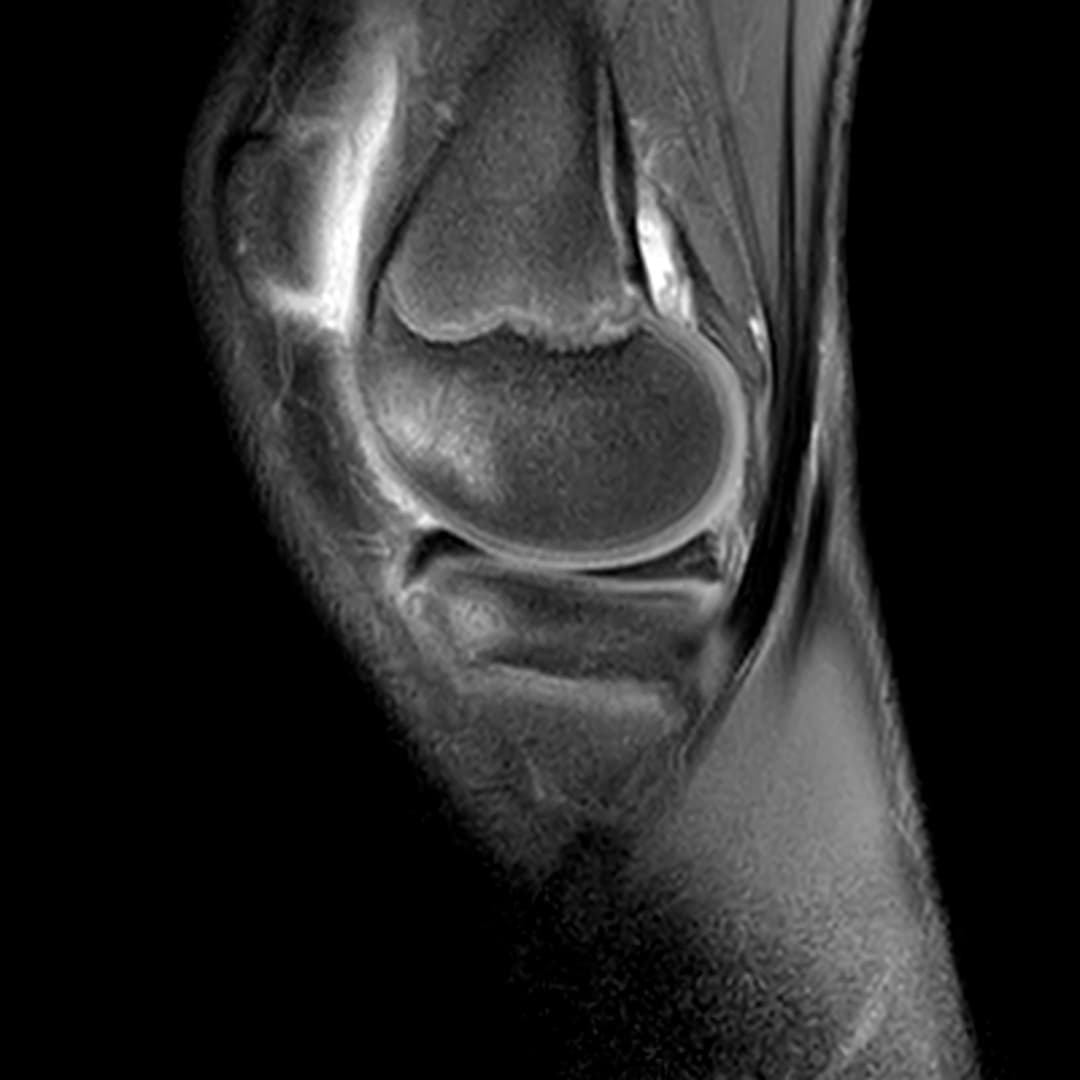

Contusion osteo-chondrale du genou

Présentation clinique

Douleurs post traumatique et gonflements

IRM

Intégrité ligamentaire et méniscale

Fracture sous chondrale par impaction avec œdème sous chondral en miroir du compartiment fémoro-tibial médial.

Epanchement articulaire abondant.